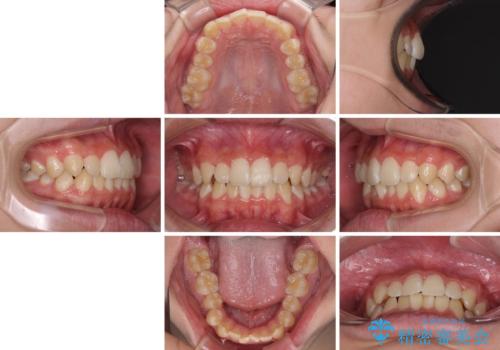

- 上下前歯のデコボコを気にして来院された患者様です。

高校2年生の後半であったため、受験も近く、大学に入学してからでも良いのではと提案しました。

本人の「しっかりと装着する」という強い意志があったため、来院の負担を少なく受験までに終えられるよう、インビザラインにて矯正治療を行うこととしました。